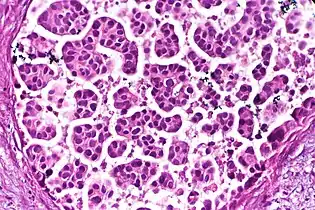

Architectural pattern of any suspicious cells, in this case nests of cells, as well as components of the intervening stroma.

Nests: islands of cells of similar type.

Cribriform: Solid with multiple clear spaces.